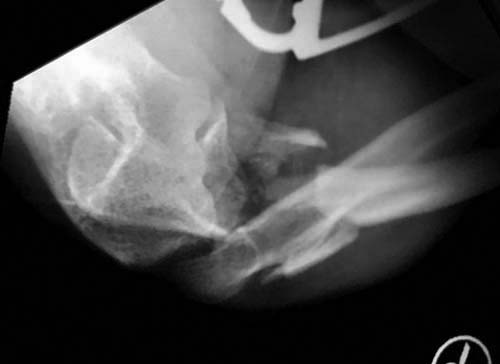

А так, здесь имеется многофрагментарный проксимальный перелом локтевого

отростка с переломо-вывихом головки лучевой кости по классификации Mason

III. Решение принимается на основании КТ срезов, потому что на боковом

рентген снимке вроде отсутствует смещение, где сустав и контур Coronoid

в одном блоке, а на прямом подозрение на смещение в Coronoid?